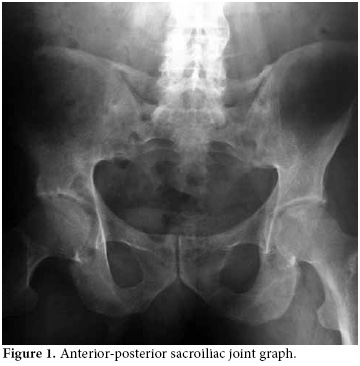

A 48-year-old male patient who had been followed up in another center with the diagnosis of AS was referred to our clinic with complaints of pain in the lower back, neck, and right hip increasing at rest and decreasing with activity. The locomotor system examination revealed that the cervical and lumbar vertebra motions were limited and painful. The motions of the right hip were painful, and extension and rotation were limited. The Mennel test and Patrick-Faber test were positive on the right side. The lumbar Schober test was 2 cm, and chest expansion was 2 cm. The anterior-posterior sacroiliac joint graph revealed bilateral stage IV sacroiliitis along with concentric narrowing in the joint space of the right hip (Figure 1), and the anterior-posterior lumbosacral graph revealed syndesmophytes (Figure 2). The patient was found to be human leukocyte antigen-B (HLA B27)(–). He had been followed up for seven years at another center with the diagnosis of renal failure associated with nephrolithiasis and had used sulfasalazine and leflunomide for AS. The patient had stopped using sulfasalazine and leflunomide on the recommendation of the nephrology department 1.5 months before attending our clinic. The patient was hospitalized for adjustment of his medical treatment. During follow-up, his temperature was 38-38.5 °C, and the patient developed abdominal pain. Detailed history revealed that the patient had been suffering recurrent attacks of fever and abdominal pain once a month for 15 years. At the time of the attack, the laboratory findings were as follows: Erythrocyte sedimentation rate (ESR): 74 mm/h, C-reactive protein (CRP): (++++), fibrinogen: 721.2 mg/dl (180-360 mg/dl), serum creatine: 1.6 mg/dl (0.5-1.2 mg/dl), blood urea nitrogen: 66 mg/dl (10-50 mg/dl), creatine clearance: 42 ml/min (71-151 ml/min), and microprotein in 24-hour urine: 333 mg/day (<150 mg/day). The patient had combined heterozygote M680I and M694V mutations of the MEFV gene which is common in FMF. There was no finding of hepatosplenomegaly on the abdominal ultrasonography. The gingival biopsy was negative for amiloidosis. The patient's daughter, who had similar attacks, was also diagnosed with FMF eight months after him. The patient was started on colchicine treatment (1.5 mg/day), and in the follow-up, he had attacks of abdominal pain and fever. His joint-related complaints regressed but did not completely resolve. The patient had been on leflunomid for 1.5 years and sulfasalazin for six months with no benefits and suffered from chronic renal failure. Thus, a TNF-α inhibitor (Adalimumab, 40 mg every other week) was added to the treatment regimen with colchicine after two months. After the patient used this combination for nearly one year, his complaints significantly improved. The patient had only one attack in that period. However, the patient's adherence to therapy was poor, and he did not use the TNF-α inhibitor for four months. He reapplied to our clinic with the complaint of increased joint pain. He reported one abdominal pain attack during these four months. The Bath Ankylosing Spondylitis Disease Activity Index (BASDAI) and laboratory findings of the patient before, during, and after dropping out of the treatment have been presented in Table 1. After the controls, the patient was restarted on TNF-α inhibitor (Adalimumab) treatment.

Familial Mediterranean fever is a disease usually seen among people with Mediterranean origin and is characterized with self-limited attacks of fever and polyserositis.[2] Articular involvement is the second most common presentation following abdominal pain.[13] One of the musculoskeletal involvement forms of FMF is spondyloarthropathy, and, almost always, HLA-B27 is negative. In these patients, generally minimal radiological spinal involvement is accompanied with unilateral or bilateral sacroiliitis, recurrent entesitis, and inflammatory low back and neck pain.[5] It has also been reported that AS may accompany FMF.[5,8,14] In our patient, a positive Schober's test, limited chest expansion, and the presence of bilateral stage IV sacroiliitis on the anterior-posterior sacroiliac joint graph with syndesmophytes on the anterior-posterior lumbosacral graph suggested FMF accompanied by AS.